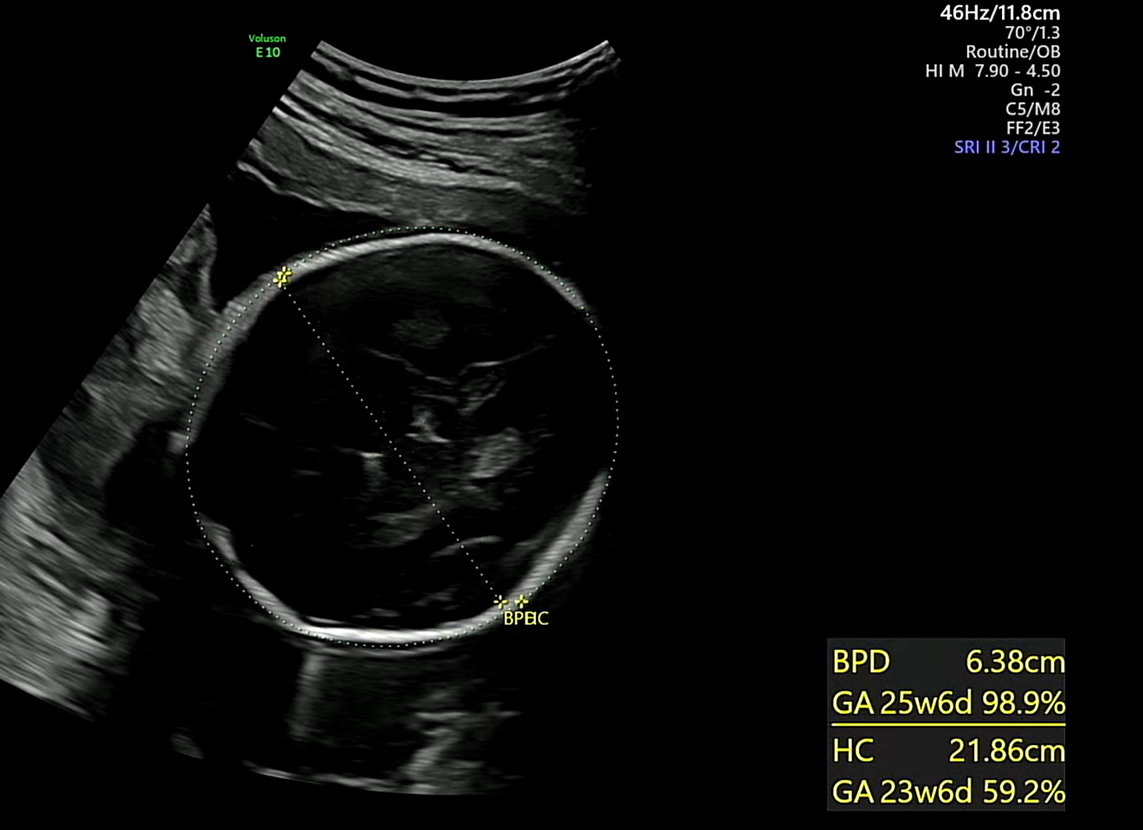

머리

정밀초음파 시작으로 가장 먼저 확인한게 바로 머리크기다. 머리가 잘 자라고 있는지 확인하는 것인데 머리크기는 25주 6일차 평균 태아의 성장상태인것과 같이 잘자라고 있음을 확인하였다.

※ 초음파 용어) BPD : 태아 머리 직경 , HC : 태아 머리 둘레